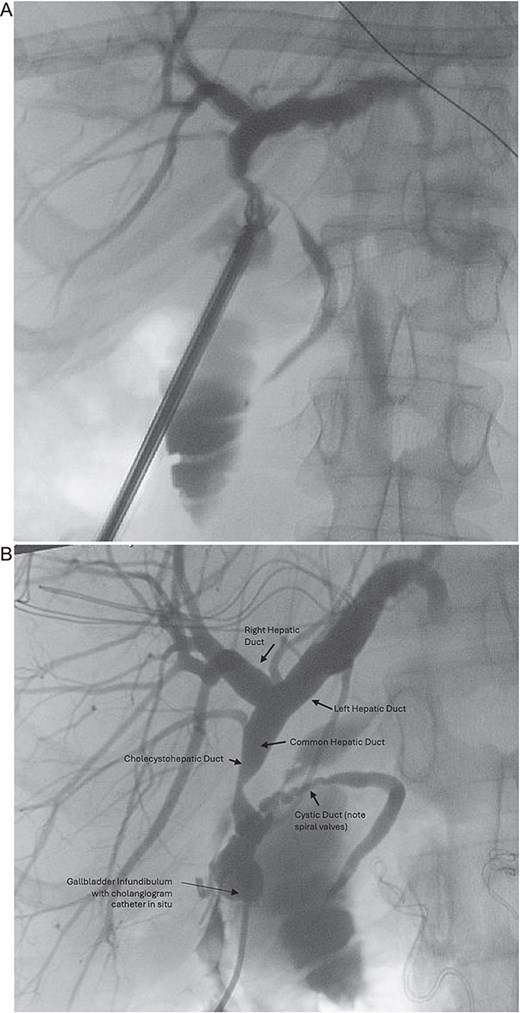

A four-port laparoscopic cholecystectomy was performed on Day 3 after symptom resolution. After obtaining the critical view of safety, an incision of the infundibulo-cystic junction was made and intra-operative cholangiogram performed, however biliary anatomy was difficult to interpret (Fig. 1A). The cystic ductotomy was closed and a higher incision on the gallbladder infundibulum made to better delineate the anatomy with a high cholangiogram. Again, biliary anatomy could not be easily interpreted, prompting conversion to open. A third cholangiogram with the gallbladder compressed to facilitate preferential filling of the cystic duct (CD) and common hepatic duct (CHD) was performed, revealing the CHD was draining directly into the gallbladder infundibulum from the liver and that the entire biliary drainage from the liver and gallbladder to ampulla of Vater was via the cystic duct, identified via its spiral valves (Fig. 1B). There was a stricture just proximal to where the CHD drained into the infundibulum, but otherwise the biliary tree was intact with nil evidence of redundancy or stricturing of the CBD (Fig. 2A). There were no large stones, inflammatory erosion, or evidence of cholecystobiliary fistulization to suggest Mirizzi syndrome. After intra-operative consultation with two other consultant hepatobiliary surgeons, a reconstituting subtotal cholecystectomy was performed, ensuring the infundibulum, with the draining CHD and cystic ducts, was preserved (Fig. 2B).

(A) Initial intra-operative cholangiogram, difficult to interpret biliary anatomy. (B) Intra-operative cholangiogram once converted to open, revealed the common hepatic duct was draining directly into the gallbladder infundibulum from the liver, and that the entire biliary drainage from the gallbladder to the ampulla of Vater was via the cystic duct.